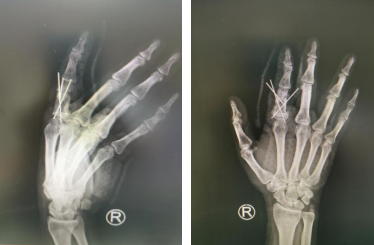

次日,完善了术前各项准备,郑主任、张继朝医生团队为刘先生进行了手术治疗,术中发现近节指骨中段骨质已被肿瘤破坏,首先进行了肿瘤病症的扩大刮除,并对骨面进行抗肿瘤治疗以减少复发几率,然后进行指骨重建,以髂骨植入骨缺损处,纠正畸形并恢复患指长度。手术顺利,术后刘先生手指又恢复了功能及美观。

术后二月

术后即刻